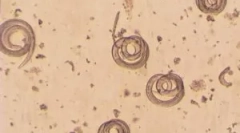

Limfna filariatoza

Seznam, katere bolezni se prenesejo na komarje, je nemogoče, da ne omenjam limftičnega klapara. Ta bolezen, znana tudi kot elephantizem, je vključena na seznam pozabljenih tropskih bolezni. Poti - okrogli črvi iz filarioidea. Glavni prevozniki - komarica Culex, Anofeles in AEDES. Komar, ugriz bolnika, okužen z mikrofilarias, to je nezrele ličinke. Enkrat v organizmu žuželk, paraziti razvijejo, postajajo polne ličinke.

Po okuženem Komarju bo ugriznil osebo, ličinke prodrejo v telo, selitev v limfni sistem, kjer se spremenijo v odrasle nematode. V procesu nepravilnosti parazitov je prizadet imunski in limfni sistem, slonova (zgoščevanje tkanin), limfni edem, vnetja kože razvija. Bolezen pogosto vodi do invalidnosti in celo smrti.